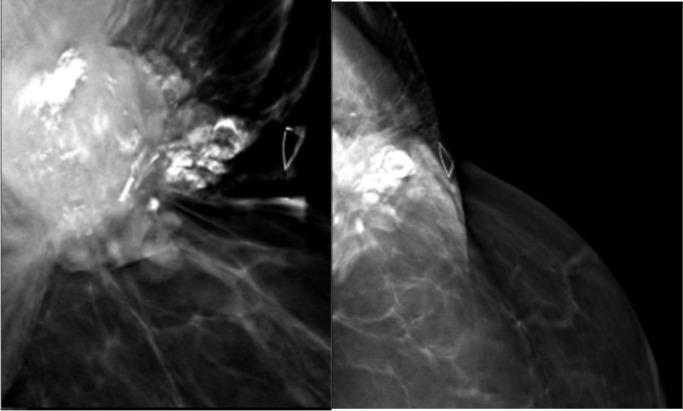

Metaplastic breast carcinoma is rare and may present as a highly aggressive subtype of breast cancer. In this case report of metastatic metaplastic breast carcinoma with osteosarcomatous differentiation in a female patient previously treated for invasive ductal carcinoma, we describe the new presentation of a palpable mass with associated calcifications on imaging near the site of prior partial mastectomy. This article will detail the clinical presentation, imaging findings, histopathology, and clinical course following treatment of our case. Knowledge of the clinical and imaging presentation of this rare subtype, which can present with benign features on mammography and ultrasound, can facilitate timely diagnosis as treatment paradigms evolve.

化生性乳腺癌较为罕见,可能是一种侵袭性很强的乳腺癌亚型。在本病例报告中,一名曾接受浸润性导管癌治疗的女性患者发生了具有骨肉瘤分化的转移性化生性乳腺癌,我们描述了在先前保乳手术部位附近出现可触及肿块并伴有影像学钙化的新表现。本文将详细介绍我们病例的临床表现、影像学检查结果、组织病理学以及治疗后的临床病程。随着治疗模式的发展,了解这种罕见亚型在乳腺X线摄影和超声检查中可能表现出良性特征的临床和影像学表现,有助于及时诊断。